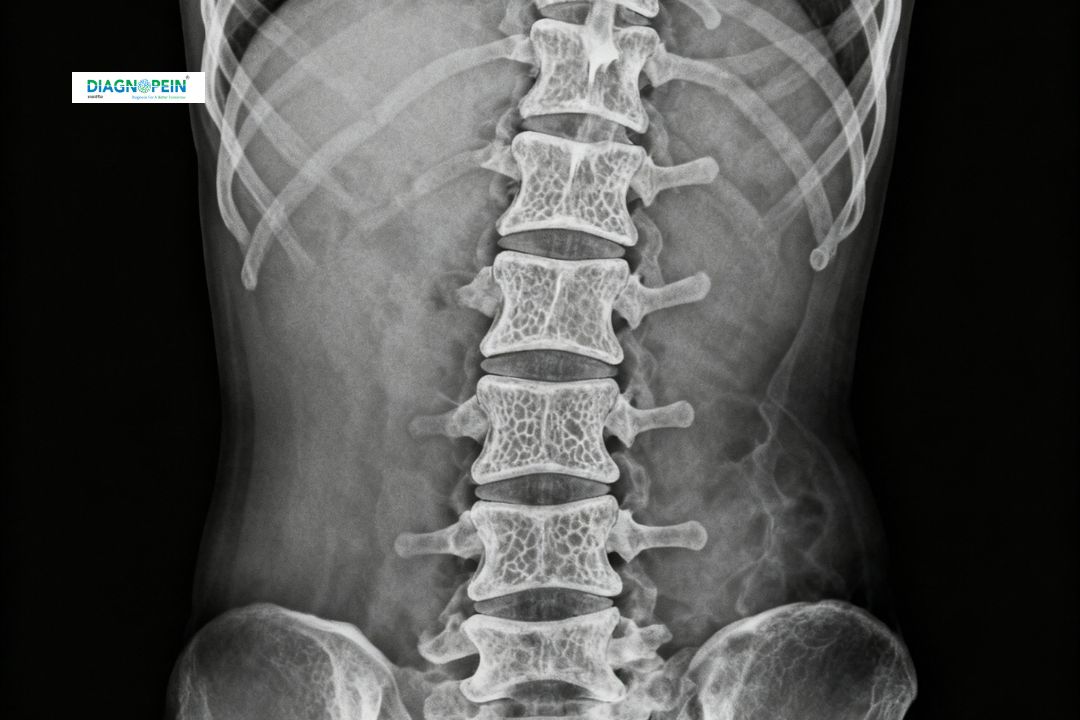

X-Ray L.S. Spine Lateral (Lumbar Spine Lateral View) is a common diagnostic imaging test used to evaluate the lower back region. It provides a detailed side-view image of the lumbar vertebrae, sacrum, discs, and surrounding soft tissues. At Diagnopein in Karad, this test helps detect spinal issues such as fractures, disc degeneration, alignment problems, or bone deformities that cause back pain and restricted movement.

The L.S. Spine LAT view is particularly helpful for visualizing the lumbar curvature and vertebral alignment from the side. It assists doctors in identifying early signs of spondylosis, slipped discs, or other degenerative spinal disorders.

The lumbar region of the spine bears most of the body’s weight and plays a crucial role in movement and support. Accurate imaging of this area is vital for proper diagnosis of lower back pain and related symptoms. An X-Ray L.S. Spine LAT in Karad at Diagnopein helps doctors:

1. Detect bone fractures after an injury or accident

2. Evaluate spinal alignment and curvature (lordosis or scoliosis)

3. Identify degenerative diseases like arthritis or osteoporosis

4. Monitor postoperative spinal conditions and surgical outcomes

5. Assess bone density and detect bone infections or tumors

Getting a lateral view enables precise evaluation from a different angle, offering a more comprehensive understanding of spine health.

1. Vertebral alignment and curvature

2. Intervertebral disc space

3. Bone density and degenerative changes

4. Presence of fractures or deformities

5. Condition of the sacrum and sacroiliac joints

These findings help doctors in Karad to create accurate treatment plans for chronic back pain, spinal injuries, or suspected arthritis.